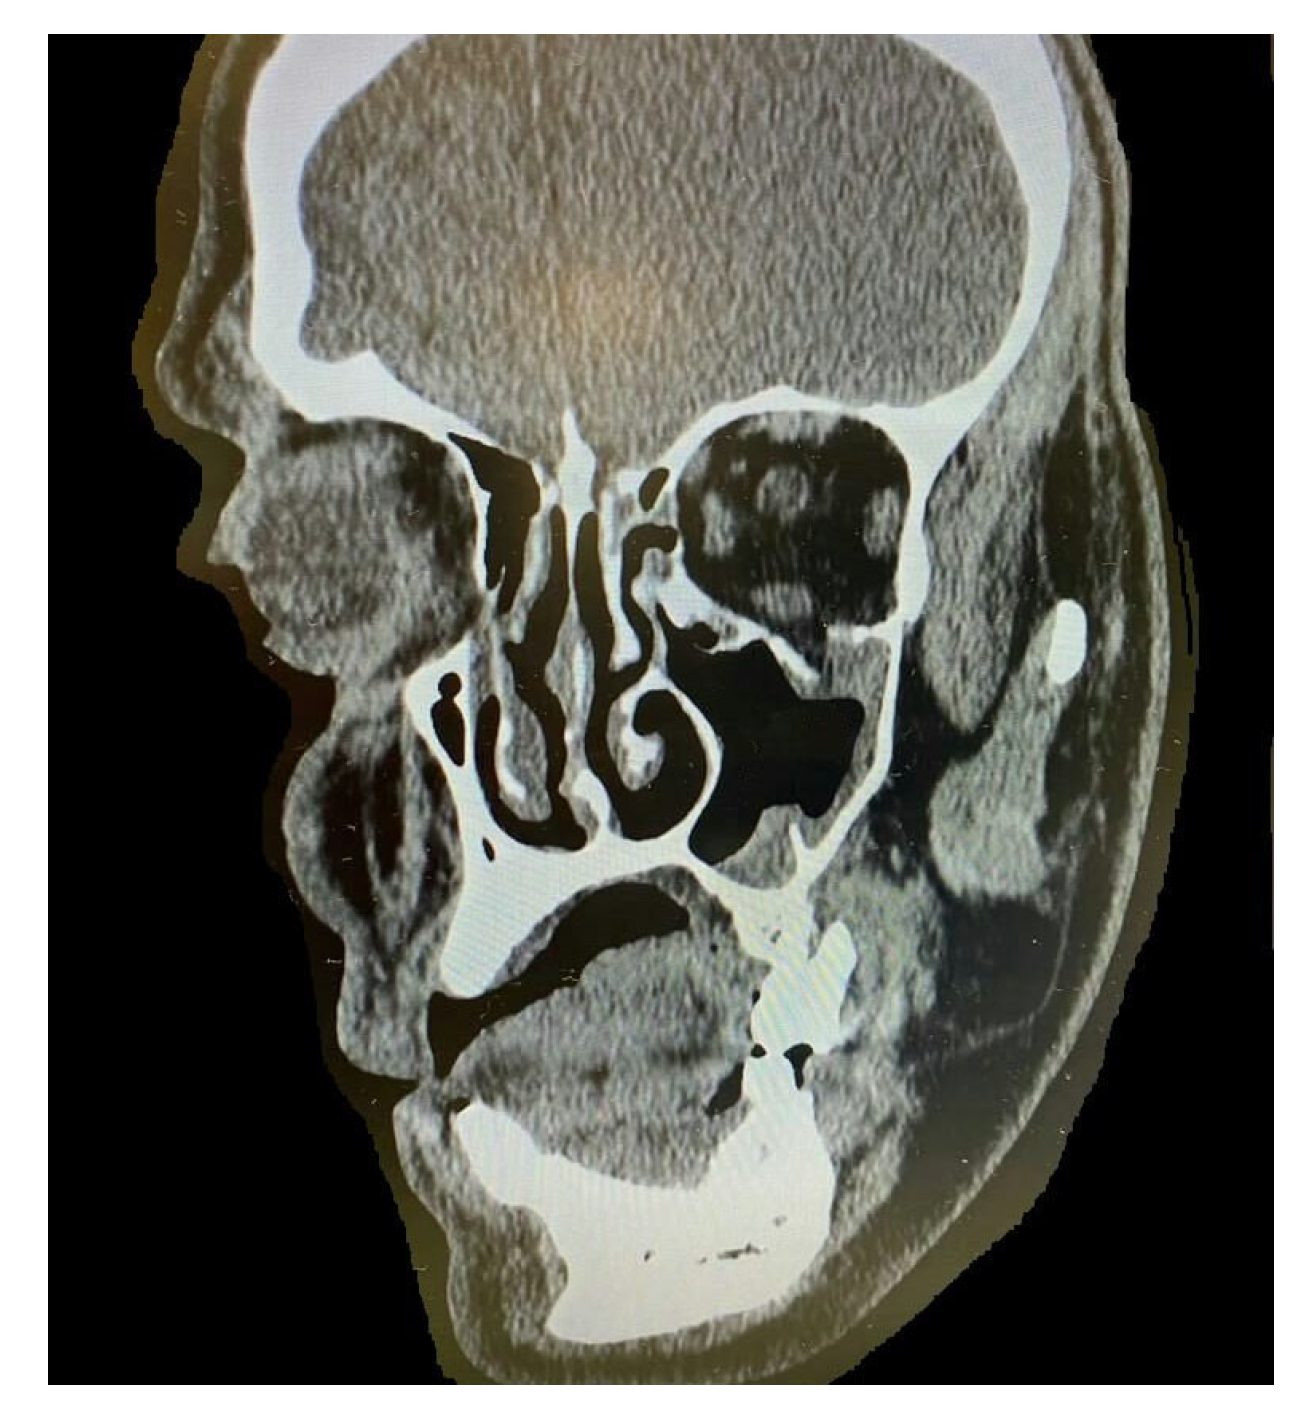

By counting the occurrence of the sites of fracture, either alone or combined, we found that the orbital floor (n = 52, 41.9%; Figure 1) and lateral wall (n = 31, 25.0%) were the most prevalent sites of bone fracture among the study patients (Figure 2, Figure 3 and Figure 4). Figure 5 illustrates the distribution of the causes of trauma.

Figure 2.

Cone-beam computed tomography (CBCT) of orbital floor fracture.